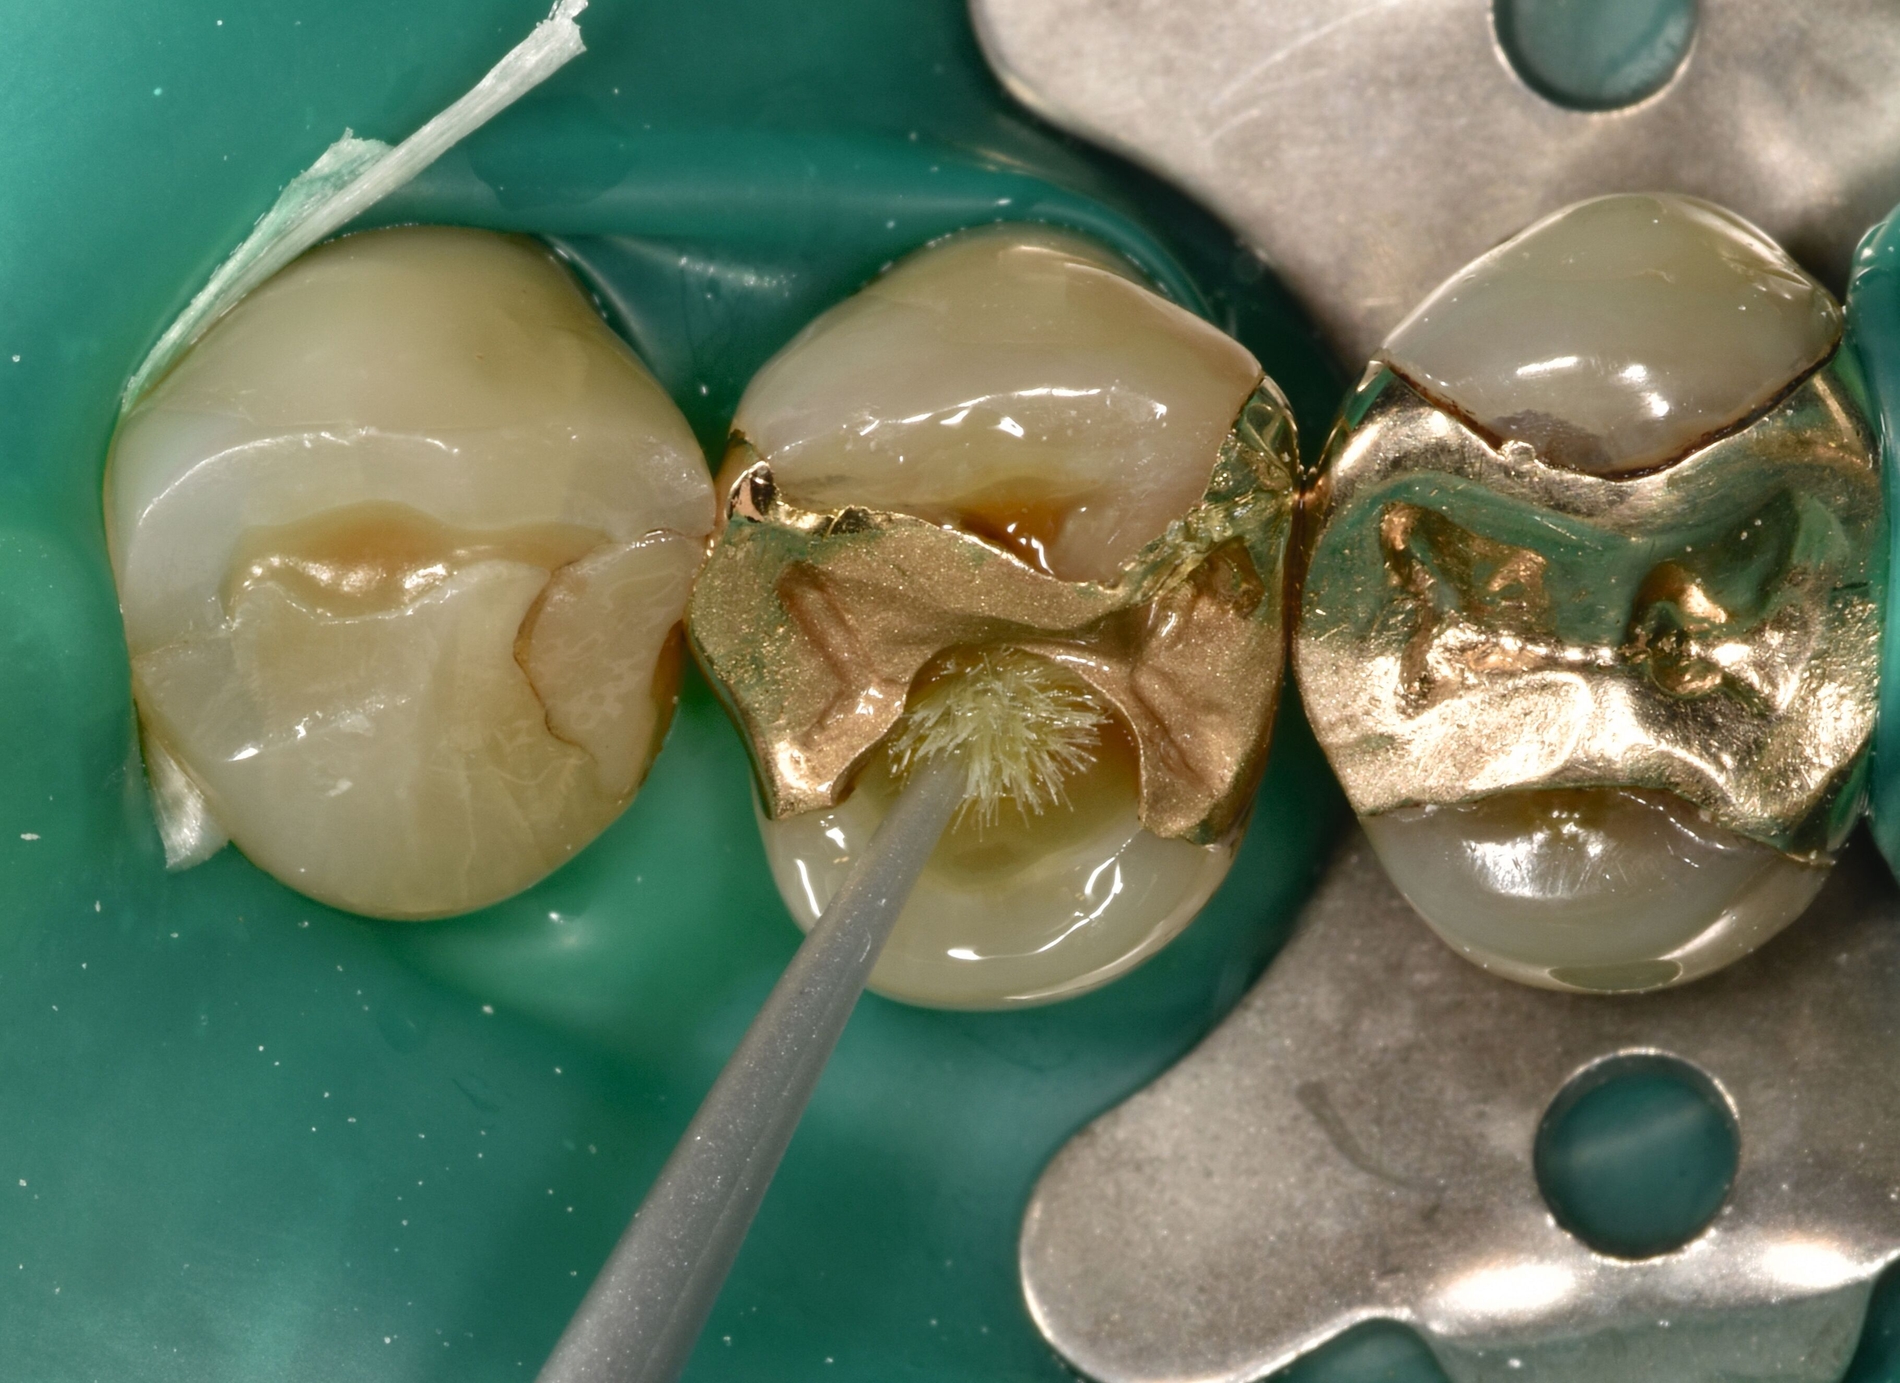

Nach Reinigung der Zähne und Bestimmung der Zahnfarbe wurde Kofferdam zur absoluten Trockenlegung angelegt. Mit rotierenden Instrumenten wurde ein Teil des Gussmetall-Inlays im sondierbaren Bereich entfernt und die Karies exkaviert (Abbildungen 2c und 2d). Anschließend wurden alle zu reparierenden Oberflächen (Gussmetall, Dentin und Schmelz) mit reinem Aluminiumoxid, Partikelgröße 50 µm (Rondoflex®/KaVo), unter Verwendung von Wasser abgestrahlt und danach gründlich mit Wasser abgespült (Abbildungen 2e und 2f). Die selektive Schmelzätzung erfolgte mit 37,5-prozentiger Phosphorsäure (Email Preparator®/Ultradent) für 30 Sekunden (Abbildung 2g). Nach Abspülen der Phosphorsäure mit Wasser wurde ein Universaladhäsiv (Clearfil Universal Bond Quick® / Kuraray Noritake) aufgetragen (Abbildung 2h, Glanz soll erhalten bleiben, Verdunstung einige Sekunden abwarten) und dann lichtpolymerisiert.

Im Anschluss wurde die Reparaturrestauration mit Komposit (Ceram X Spectra®/Dentsply Sirona) eingebracht (Abbildung 2i). Im Sinne des Restaurationsunterhalts wurden bei der Politur die Restaurationsränder der Gussmetall-Inlays an den Zähnen 24 und 25 finiert und zusammen mit der Kompositrestauration hochglanzpoliert (Abbildungen 2j und 2k).